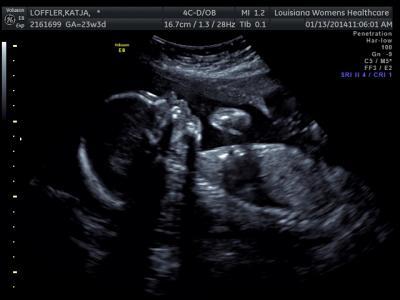

Heute hatte ich wieder Termin zum US. Eigentlich sollte nur der Gebaermutterhals kontrolliert werden, aber die gute Frau hat komplett das Baby geschallt. Es ist immernoch ein Junge, er ist etwa 28 cm gross (von der Femurlaenge berechnet), 560 g schwer. Er ist in Steisslage, hat ja aber noch reichlich Zeit sich zu drehen. Heute ist er eher klein fuer die SSW, vor 3 Wochen war er eher gross. Kleiner ist besser fuer mich, da ich dann hoffentlich eine laengere Schwangerschaft haben werde. Mein GBH ist stolze 4.5 cm :)! Er hat sich also vom letzten Mal (3.3 cm) wieder verlaengert - ohne schonen oder so. Tschaka. Es sieht also alles noch gut aus :). Mein Doc hat mich wegen der Symphyse nun fuer Physio (im Wasser) angemeldet und ich warte auf den Anruf, um den ersten Termin festzulegen. Morgen rufen sie sicher an. Dann habe ich mit ihm ueber das Geburtshaus geschwatz - manche erinnern sich vlt. an meinen Jammerpost von Freitag oder so. Sie kennen Leute in der Stadtverwaltung und die Bauantraege sollten schnell durch sein!!! Neuer angestrebter Oeffnungstermin ist der 17. Maerz. Hoffen wir mal. Ich verlasse mich nicht drauf, aber HOFFE einfach mal, dass sie es bis Anfang April hinkriegen, sonst kann ich es vergessen. Grmpf. Dann habe ich noch die rausgewachsenen Sachen meiner Tochter in einem neuen Second Hand Laden vorbeigebracht. TOLLER LADEN! Eine Auswahl - und niedrige Preise. Leider machen sie derzeit nur Ankauf, Verkauf dann ab Februar. Grmpf. Oh, da drinnen konnte man sabbern *g*. Waehrend die meine Klamotten durchgesehen habe, bin ich in einen anderen Second Hand Laden in der Naehe und habe da super Schnaeppchen fuer Baby Boy und meine Tochter gemacht. $80 bezahlt fuer super viele Marken-Teile, Klamotten fuer etwa $40 noch gratis drauf bekommen :D :D :D. Gratulation an alle, die fertig gelesen haben. Als Belohnung gibt es noch ein Bildchen. Katja

Bild zu US, FA, Geburtshaus, Shopping - und BILD :D - Forum für Mai - Mamis